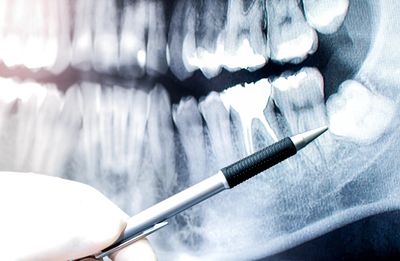

Wisdom teeth removal is a common procedure aimed at preventing pain, infection, and long-term dental problems. These back molars often don’t have enough room to grow in properly, which can lead to crowding, swelling, decay, or even damage to neighboring teeth.

At Tooth Room Dental, we carefully assess your wisdom teeth with digital imaging to understand their position and determine whether removal is recommended. If extraction is the best option, we take a gentle, patient-focused approach to keep you comfortable throughout the process. Our team will guide you through what to expect, how to prepare, and how to care for yourself afterward for a smooth recovery.